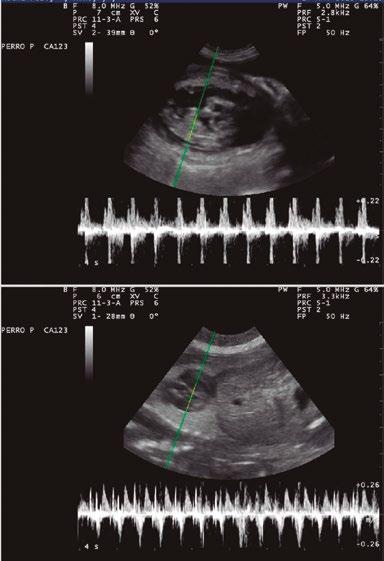

3. Estudio ecográfico

Permite evaluar la viabilidad de los fetos o un posible sufrimiento fetal (figura 3). La frecuencia cardiaca (FC) de los fetos es superior a 200 latidos por minuto (lpm). Se considera estrés fetal si la FC está por debajo de 180 lpm. Por debajo de

160 lpm existe sufrimiento fetal grave y se debería realizar una cesárea de urgencia.

Figura 3. Ecografía de los fetos.